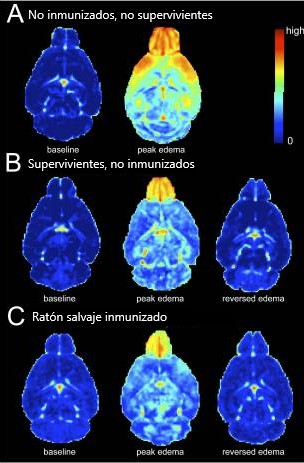

Según investigaciones con ratones, se ha descubierto que el interferón, una sustancia utilizada en el tratamiento y combate del cáncer, puede potencialmente desencadenar malaria cerebral al interactuar con ciertos receptores en el cerebro (Palomo et al., 2013).

No obstante, es importante desatacar que la malaria cerebral solo se ha podido investigar en ratones, donde se ha observado el desarrollo de micro edemas en el cerebro. Es en base a dicho paralelismo, se puede explicar el daño que probablemente presente una persona contagiada, permitiendo comprender la severidad de la enfermedad y plantear estrategias de tratamiento adecuadas (Jin et al., 2022).